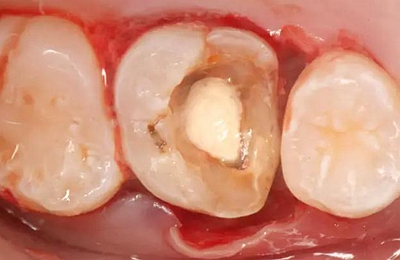

病例一 女性,20歲,大學生,要求補牙,檢查口內(nèi)可見A6大面積缺損,近中牙齦息肉,拍X片,根管充填物略差,但根周未見明顯陰影,口內(nèi)檢查無叩痛。建議患者冠延長手術+高嵌體修復。

患牙遠中邊緣嵴完整,強度沒有降低,故擬保留遠中邊緣嵴,高嵌體修復。首先去除腐質(zhì)及原墊底材料,流體樹脂+3M Z350XT樹脂墊底。局麻下行冠延長手術。在此需要提及個人的一個觀點。冠延長手術原則上要求3-6個月以上才能永久修復。但是個人喜歡后牙肩臺建立在齦上,所以修復后的修復體邊緣位于牙齦上方1mm,對牙周的愈合影響較?。ㄈ绻麨辇l下邊緣則要慎重),故該患者術中按照齦上邊緣的設計進行冠延長手術。以下為術中: